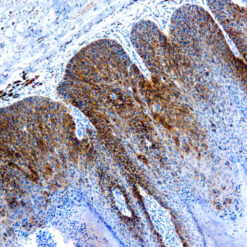

This MAb recognizes human 17-26kDa protein, which is identified as cytokine TNF-α (Tumor Necrosis Factor-alpha). Monomeric human TNF-α is a 157 amino acid protein (non-glycosylated) with a reported molecular weight of 17 kDa and can be expressed as a free molecule, also TNF-α is generated as a precursor form called transmembrane TNF-α can be expressed as a cell surface type II polypeptide consisting of 233 amino acid residues molecular weight 26 kDa. TNF-α is an important cell-signaling component of the immune system. It is a protein secreted by LPS stimulated macrophages, and causes tumor necrosis when injected into tumor bearing mice. TNF-α is currently being evaluated in treatment of certain cancers and AIDS Related Complex.

| Positive Control Tissue | Colon, Histiocytoma, Pancreas |